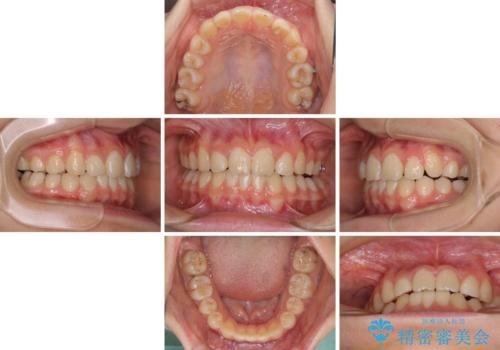

目立つ八重歯を治したい インビザラインによる矯正治療

まずは補助装置を用いて八重歯を改善し、インビザラインにて歯列を整えましたが、当初の懸念が的中し、臼歯部の咬合を安定させることができませんでした。

海外留学の予定もあったため、後半は上下ワイヤー装置にて矯正治療を継続し、違和感なく咬合させることとなりました。